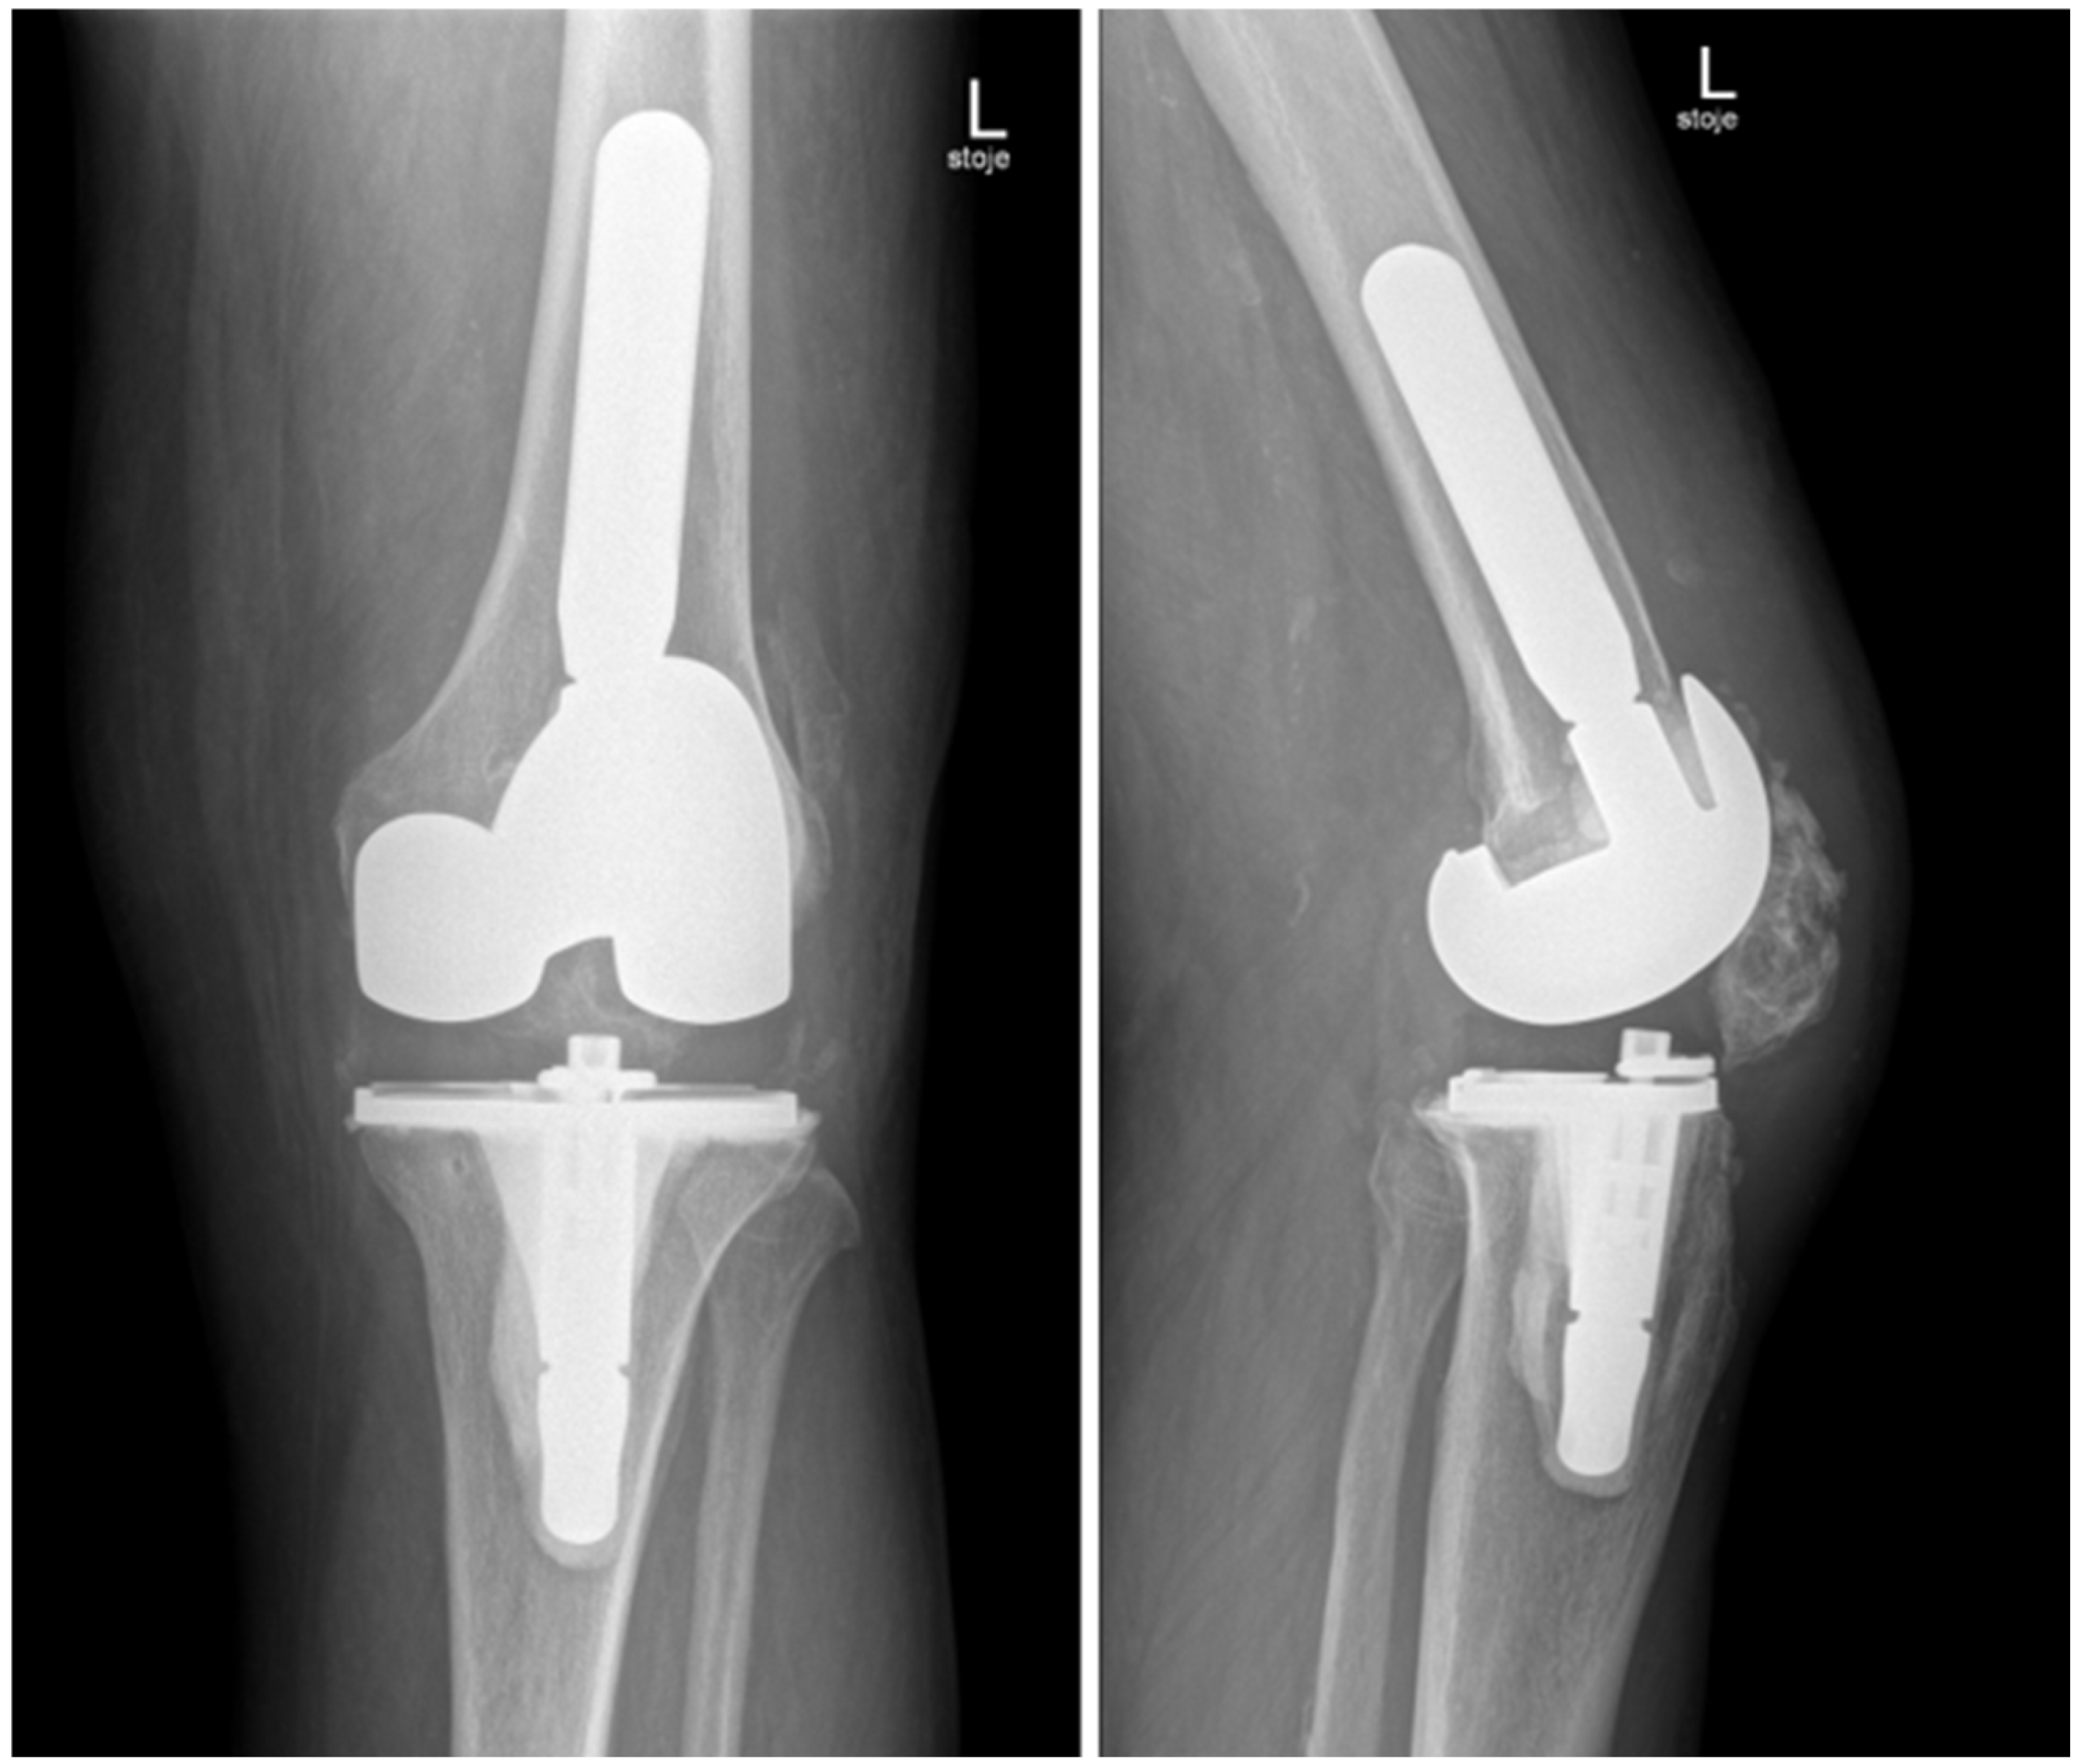

Candida parapsilosis grew in both synovial fluid samples from separate aspirations and was identified by standard microbiology methods at the microbiology laboratory at the National laboratory of health, environment and food, Maribor. Unfortunately, a mycogram was not obtained, as it is not performed in all samples routinely at the laboratory. According to the retrospective analysis of bloodstream fungal infection from central Slovenia, the Candida parapsilosis resistance rate to fluconazole was very low, and we decided to start the treatment preoperatively with oral fluconazole 400 mg/day [11]. A decision to perform a two-stage revision surgery with a 4-week interval was taken. The first stage was performed in October 2024, involving the complete removal of the implant, debridement, and insertion of an antibiotic- and antifungal-impregnated cemented spacer. For the spacer, we used Palacos R+G® cement (Heraeus Medical GmbH, Wehrheim, Germany), with each package containing 40.8 g of cement powder, 20 mL of monomer liquid, and 0.5 g of industrially premixed gentamicin. Additionally, we supplemented it with 0.25 g of non-liposomal amphotericin B deoxycholate powder (Fungizone®, Delpharm, Boulogne-Billancourt, France) per package. A total of three packages were used, resulting in a cumulative amphotericin B dose of 0.75 g. The cement powder, antifungal powder, and monomer liquid were thoroughly blended by hand, resulting in a yellowish-colored bone cement of proper hardness. In Figure 3, the preparation of an antifungal-impregnated cemented spacer is shown. During the operation procedure, 5 intraoperative tissue samples, synovial tissue samples, 2 bone tissue samples with residual non-resorbable suture material, and the explanted prosthesis were collected for further microbiological analysis; sonication of the explanted material was performed and sonication fluid cultured according to a standardized protocol. Candida parapsilosis grew from all tissue samples, bone samples, and from the sonication fluid of the removed implant in low concentration, 3 CFU/mL. Tissue samples were also sent for histopathology exam, and acute inflammation was confirmed. Antifungal therapy with intravenous caspofungin (70 mg) was started preoperatively, then 50 mg/day for two weeks, followed by an oral switch to fluconazole at 400 mg/day. The patient continued fluconazole therapy until the second stage of surgery, with no drug holiday before reimplantation was planned. In Figure 4, the left knee is presented in radiography after the first-stage surgery with insertion of an antibiotic- and antifungal-impregnated cemented spacer.

Figure 4. Radiography of the left knee—anteroposterior and lateral views of the knee after removal of knee endoprosthesis and insertion of an antibiotic- and antifungal-impregnated cemented spacer.